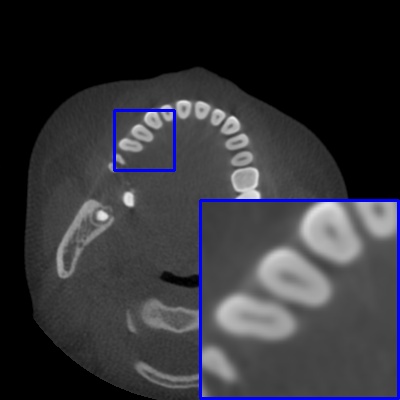

Figure 4: Comparison of MAR images by different methods on real-world MA image. The last image is the metal mask by selecting the pixel area over 2800HU in the MA image.

Results on real-world MAR. We also compare these methods on dental CBCT images with real-world metal artifacts. The visual results on one sample are shown in Fig. 4. We observe that our MARformer-T and MARformer-L well seperate the adjacent teeth and retain their shapes. This shows that our MARformers, though trained on synthetic data, are effective on real-world MAR.